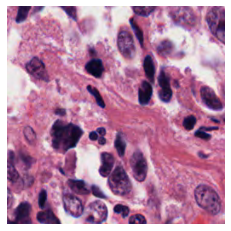

We also analyse the activation maps for each model using GradCAM as described in section S3. This offers more insight into the areas of the image which are contributing most heavily to the models’ representations. In Figure 4(b) we present some representative examples, however, a larger selection which was chosen at random is presented in Figures S10 to S25. The larger selection makes it easier to see the emergent patterns, including that privileged Siamese models tend to mainly identify features which are strongly present in both inputs, while unprivileged Siamese models tend to learn more diffuse features that are not specific to one cell phenotype or image region. TriDeNT ♆ incorporates both sets of features, learning both features specific to the privileged data and more the general features associated with unprivileged Siamese networks.

We can see in Figure 4(b) panel A that for ERG, the privileged Siamese model focuses almost exclusively on any nuclei which could be endothelial cells. As there are very few endothelial cells in the dataset, it could be an effective strategy to identify anything that could potentially be an endothelial cell to minimise the difference between the representations of the H&E model and the IF mask model. In the corresponding unprivileged Siamese image, we see that the model identifies some of these nuclei, albeit less strongly, but also focuses heavily on the other tissue and even the background, while strongly fixating on two spots of debris in the center of the image. This model has less ‘incentive’ to learn the weak features related to endothelial cells as these occur rarely and are not easy to detect, while more generic strong features such as the presence of connective tissue and the prevalence of background are more common and predictable from augmented images. We see that TriDeNT ♆ combines these two feature sets, strongly identifying nuclei while also identifying the connective tissue.

In panel C we see a similar pattern, with the privileged Siamese model fixating solely on the nuclei, while the TriDeNT ♆ model takes a more balanced approach. The unprivileged Siamese model appears to focus on a single cluster of nuclei while neglecting others, and similarly identifies an area of fibroblasts with its distinctive pattern but does not others.

In contrast to panels A and C which represent models with poor privileged Siamese results, panels B and D represent models whose privileged Siamese results were comparable to both TriDeNT ♆ and even the supervised baseline. It is therefore interesting to note that there are far more similarities between the privileged Siamese and TriDeNT ♆ models in both cases. Particularly in panel B, TriDeNT ♆ and the privileged Siamese model return virtually identical heatmaps, with both strongly identifying epithelial nuclei and neglecting the same areas of connective tissue. The unprivileged model in this case appears to focus solely on the centre of the image, giving a significantly different heatmap to the other panels.

Panel D again shows the previous pattern, with the privileged Siamese model identifying the features strongly present in the privileged data – fibroblasts – while neglecting the nuclei present. TriDeNT ♆ also strongly identifies the connective tissue, but, unlike the privileged Siamese model, does not completely neglect the nuclei. The unprivileged Siamese model primarily identifies background, and does not appear to identify the nuclei in this example.